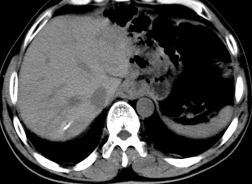

患者林##,男性,48岁,以2008.07.10于我院行“根治性全胃切除术”,病理分期:PT4N3M0,术后一个月复查CT:肝内多发占位,考虑转移癌。先后予化疗、肝动脉灌注化疗及栓塞、肝脏转移瘤射频消融、粒子植入及再次手术等综合治疗;2014.07.22复查胸部CT示右肺下叶和左肺上叶转移,化疗和肺结节粒子植入等综合治疗。现已无瘤存活8年,2016.6.19门诊随访,一般情况良好,生活质量高。

治疗前CT图片